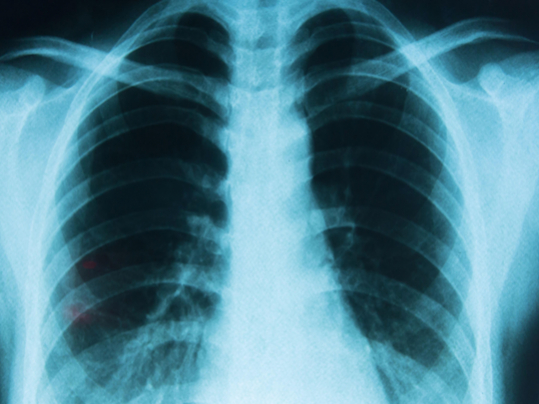

Une étude menée en Corée du Sud auprès de 8,4 millions de personnes (2021-2023) montre une augmentation significative de plusieurs cancers seulement un an après la vaccination : Thyroïde : +35% Gastrique : +34% Colorectal : +28% Poumon : +53% Poitrine : +20% Prostate : +69%

Les HR de la thyroïde (HR, 1,351 ; IC à 95%, 1,206–1,514), gastrique (HR, 1,335 ; IC à 95%, 1,130–1,576), colorectal (HR, 1,283 ; IC à 95%, 1,122–1,468), pulmonaire (HR, 1,533 ; IC à 95%, 1,254–1,874), mammaire (HR, 1,197 ; IC à 95%, 1,069–1,340) et prostatique (HR, 1,687 ; IC à 95%, 1,348–2,111)